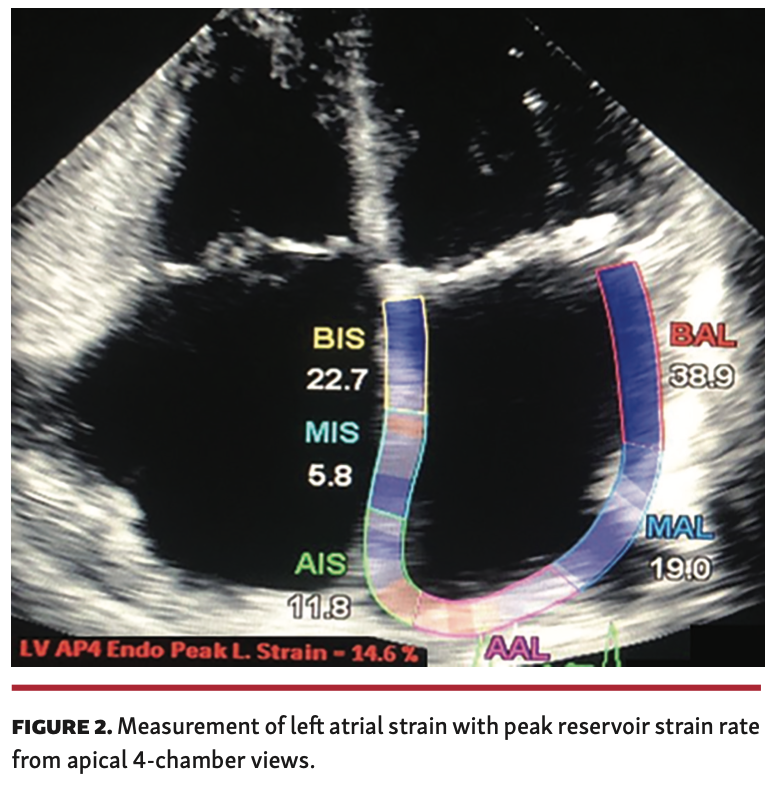

Design and study population. Between February 2015 and January 2018, a total of 302 patients were screened (Figure 1). Twelve patients with paroxysmal AF for >1 year with contraindications to oral anticoagulants and sinus rhythm during echocardiographic measurements and underwent LAA closure were enrolled in an open-label, single-center, observational, retrospective study. Before device implantation, LAA flow velocity and presence of LA thrombi were evaluated by transesophageal echocardiography (TEE). After femoral venous access, the LA was accessed by means of transseptal puncture in all patients. Experienced operators performed the LAA closures under TEE and fluoroscopy for guidance using dedicated devices (first-generation Amplatzer Cardiac Plug or second-generation Amplatzer Amulet; St. Jude Medical). Device oversizing of 3-5 mm was typically applied, as previously described.12 Patient and procedural characteristic imaging findings, laboratory results, in-hospital and follow-up data up to 6 months after LAA closure were collected in a dedicated database. TEE was performed before the procedure, periprocedurally, and during follow-up. Procedural success was defined as successful implantation of the device in the LAA without leak by postprocedure TEE. All patients were in sinus rhythm and underwent clinical assessment, conventional echocardiography, and GLS analysis of the LA at baseline and during a 6-month follow-up. The LA strain measurements were obtained from the two-dimensional (2D), apical, 4-chamber view and calculated with the negative peak strain rate during contraction phase and the reference lines for analysis were set on the P waves. The LA strain during contraction phase occurs during mitral valve closure in patients with sinus rhythm (Figure 2), as described previously.13